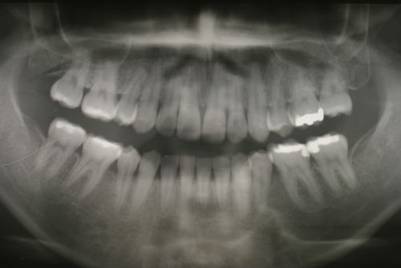

術前 97年のパノラマ

|

術後 99年 根の治療を受けていた左上第二大臼歯を抜歯し、代りに健全な親知らずを移動させました。